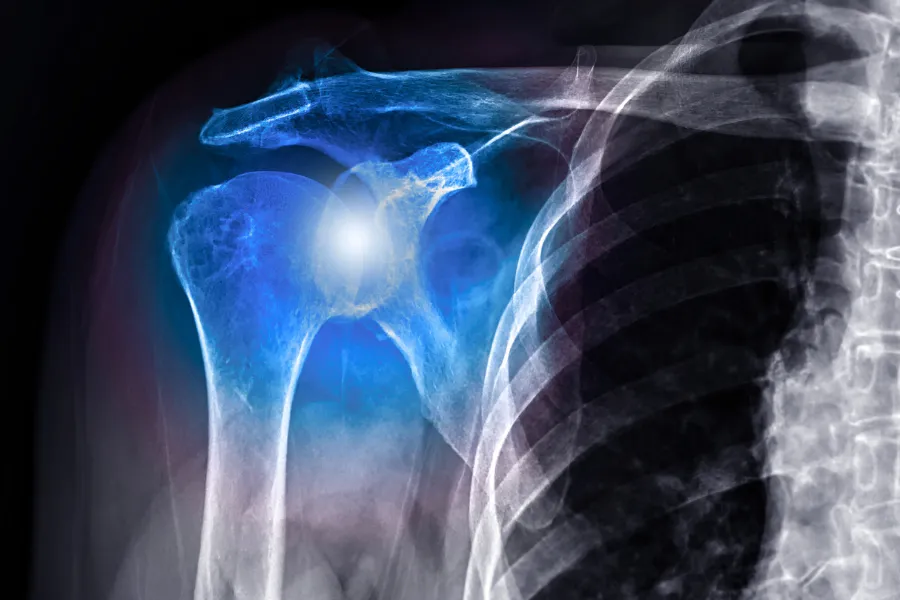

Shoulder Instability & Dislocations

Shoulder instability occurs when the structures that surround the shoulder joint do not work to keep the ball tightly in its socket. If the shoulder is too loose, it may slide partially out of place (subluxation) or completely out of place (dislocation).

The shoulder is the most mobile joint in the human body, but that mobility comes at the cost of stability. Instability typically happens when the ligaments, gasket (labrum), or capsule that holds the joint together are stretched or torn.

• X-rays, which are essential after an acute dislocation to ensure there are no fractures (such as a Hill-Sachs lesion) on the bone.